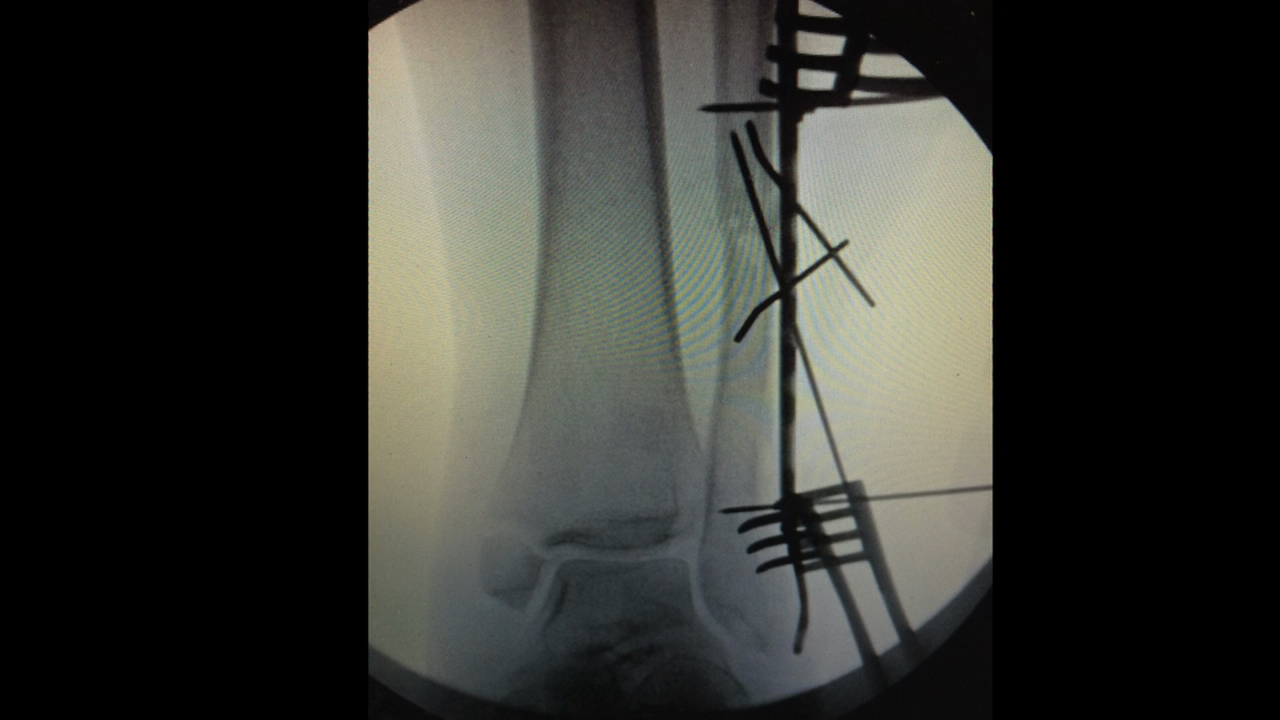

Ankle Fracture

Carbofix Ankle w VO April 2016 SS

Ankle Fx July 27 w VO

IFS Ankle Fx w VO

Sonoma Fibula Rod Jan 2016 w VO